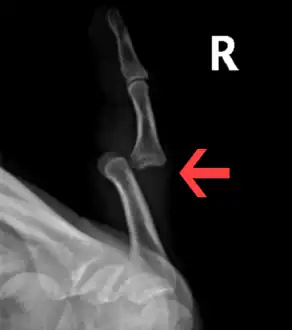

| A traumatic dislocation of the tibiotarsal joint of the ankle with distal fibular fracture. Open arrow marks the tibia and the closed arrow marks the talus. | |